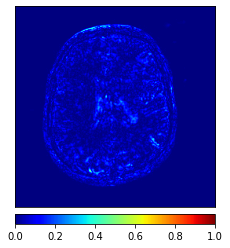

In this paper, we propose a bidirectional learning model, known as dual contrast cycleGAN (DC-cycleGAN), for medical image synthesis from unpaired data. Specifically, a dual contrast (DC) loss is formulated that leverages the advantage of samples from the source domain as negative samples to indirectly build constraints between real source and synthetic images via discriminators, and synthesize images more related to the target domain by enforcing the synthetic images to fall far away from the source domain. In addition, structural similarity index (SSIM) [35] and cross-entropy (CE) [48] are integrated into the DC-cycleGAN structure to avoid disappearing gradient information that is caused by a mean absolute error (MAE) and synthesizing irrelevant images. SSIM considers luminance [35] and CE converges fast as its back-propagation error is less than MSE [28]. As can be seen in Figs. 1 and 2, using SSIM and CE with dual contrast can generate more clear and accurate MR images as compared with that of MAE and MSE, and SSIM and CE without dual contrast loss. Although both SSIM and CE with dual contrast and without dual contrast generate similar CT images, SSIM and CE with dual contrast quantitatively generate better images as shown in Table 4. The experimental results indicate that DC-cycleGAN is able to consider more complex features such as structure in synthesizing images and produce remarkable results as compared with other state-of-the-art methods reported in the literature.

Tables 3 and 4 show the results of MR and CT synthesis, respectively. As can be seen, all components play vital role in both tables. SSIM & CE (w) performs significantly better than other losses in synthesizing MR images. This also can be seen visually in Fig. 1. In contrast, SSIM&CE (w) performs slightly better than SSIM&CE (wo) in synthesizing CT images, both generate more or less similar CT images (see Table 4).